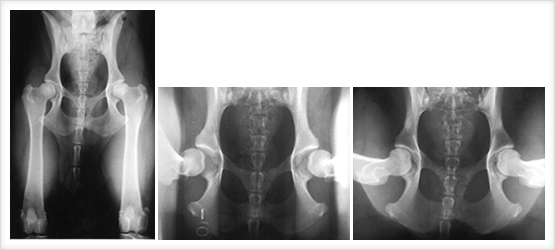

レントゲン検査・超音波検査・消化管内視鏡検査